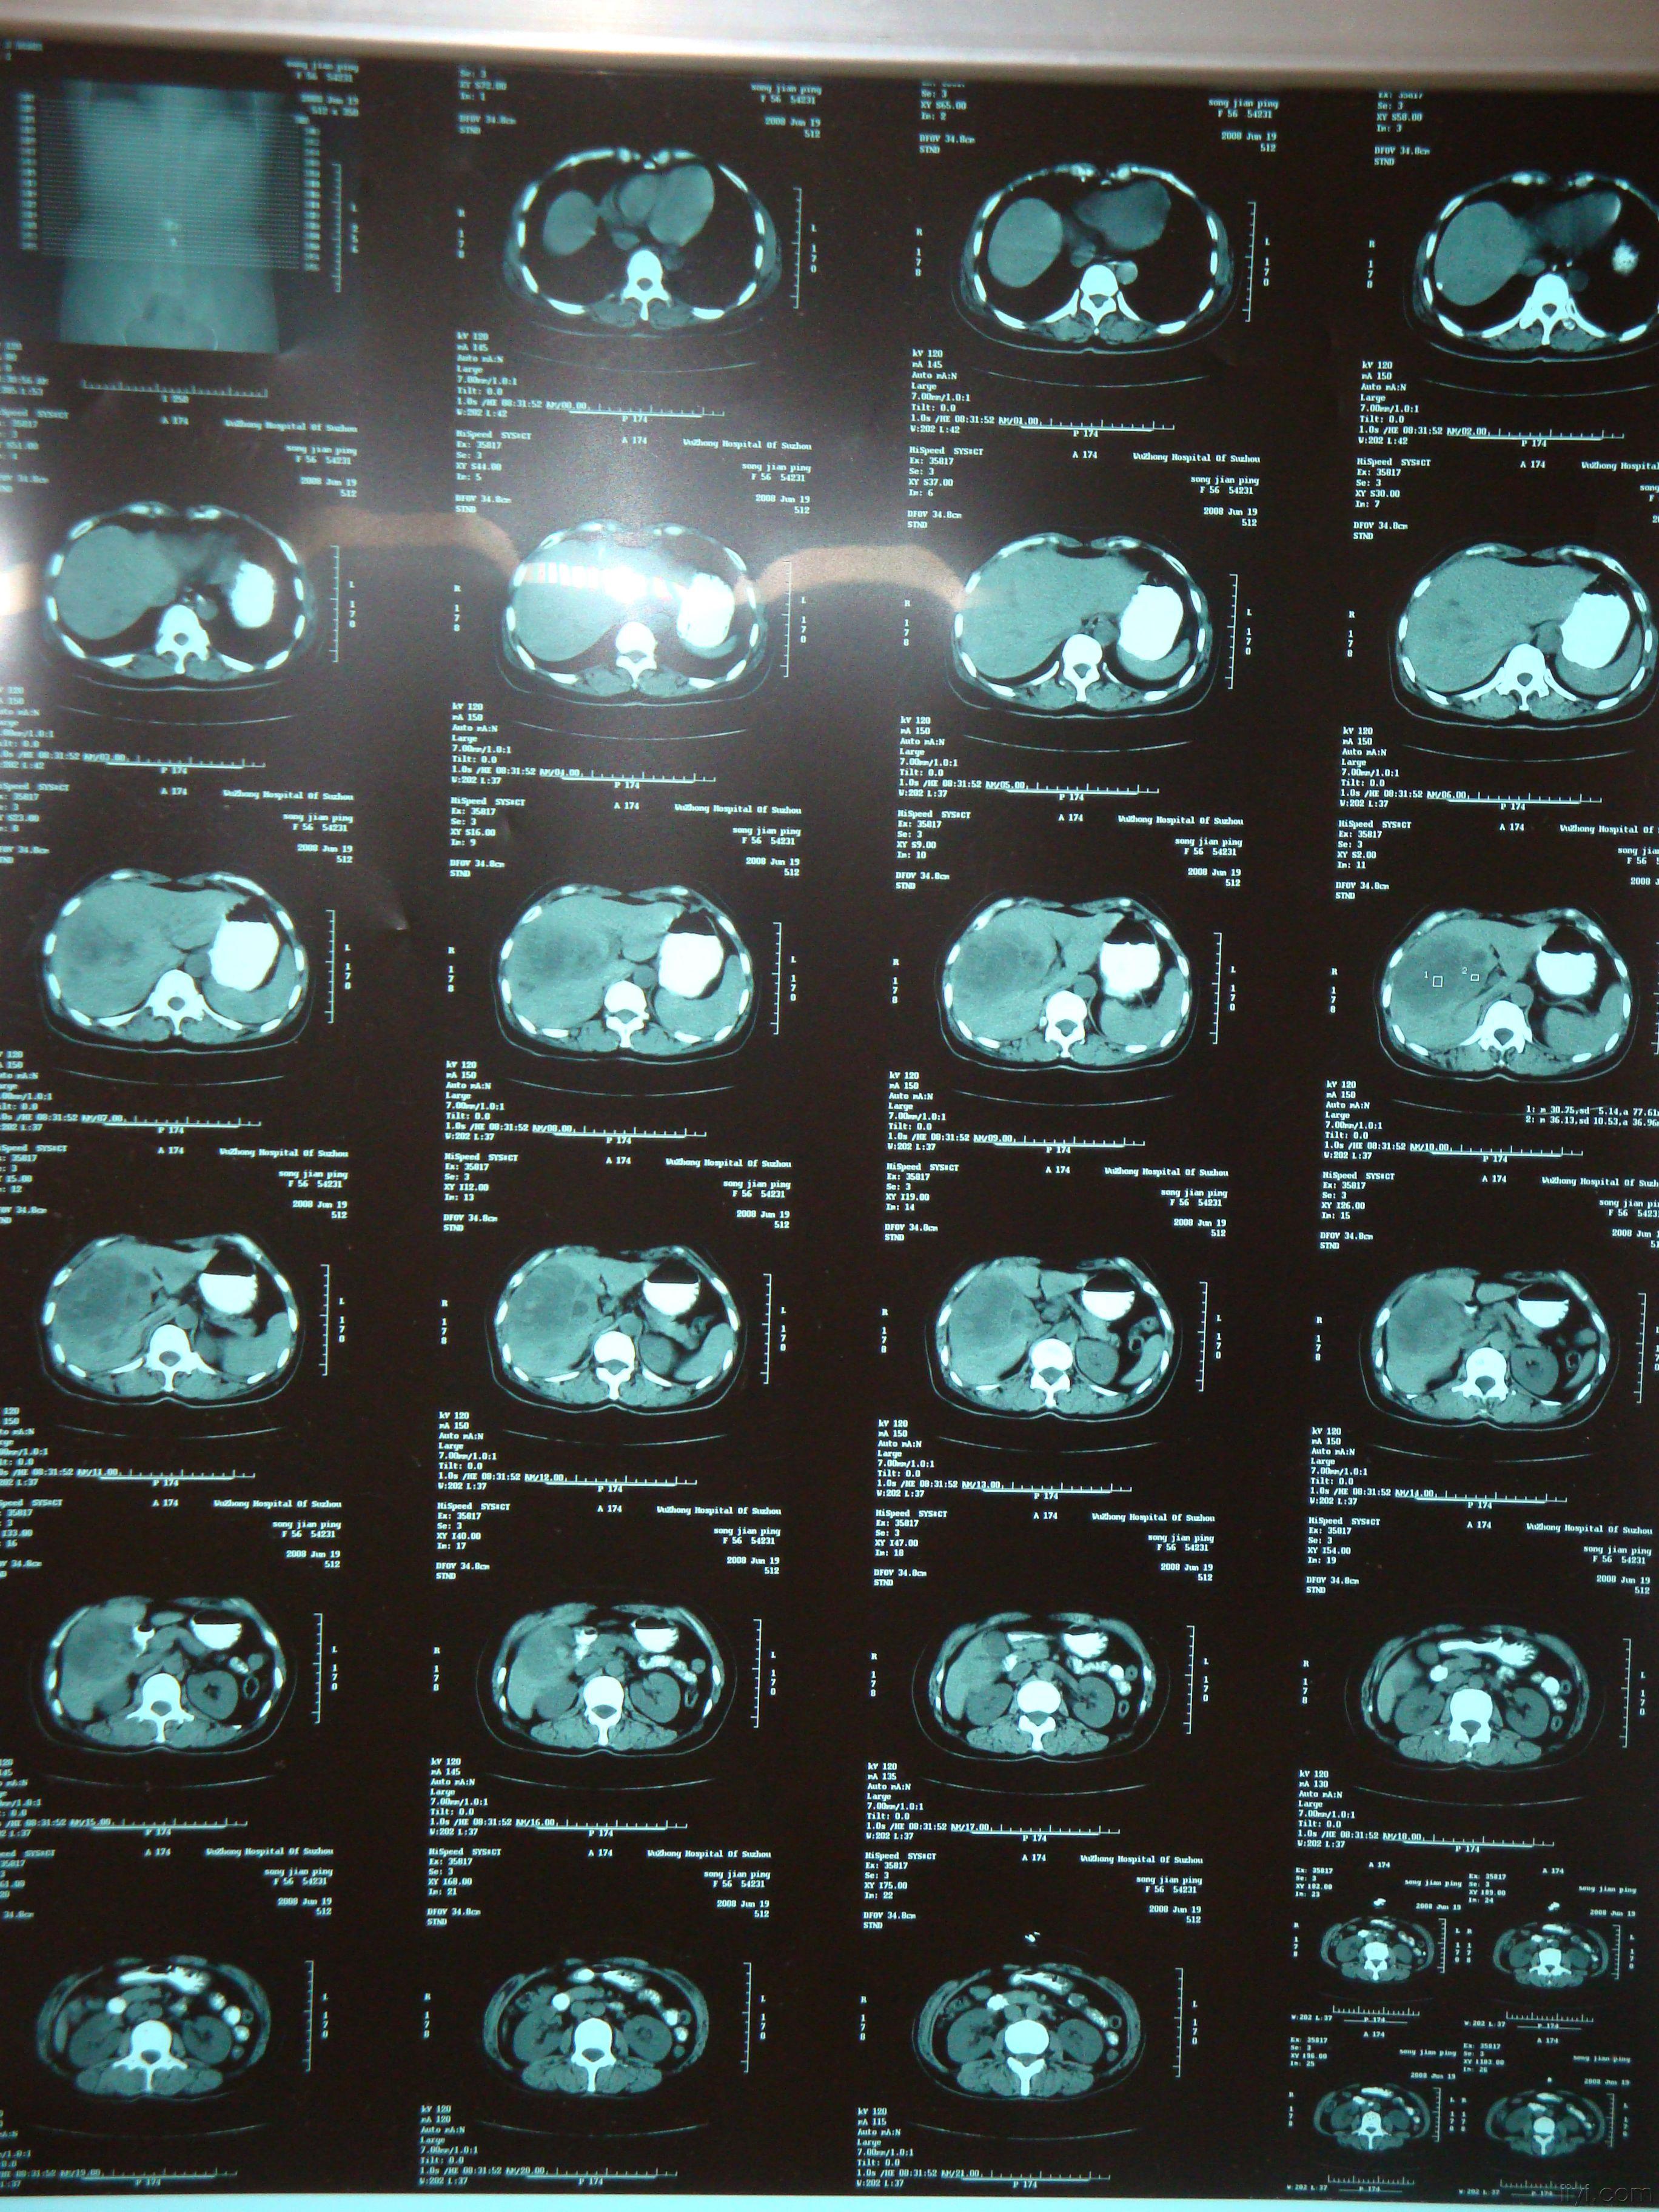

同事的ct片子,疑诊肝癌,请各位同道讨论

图片尺寸1086x1448